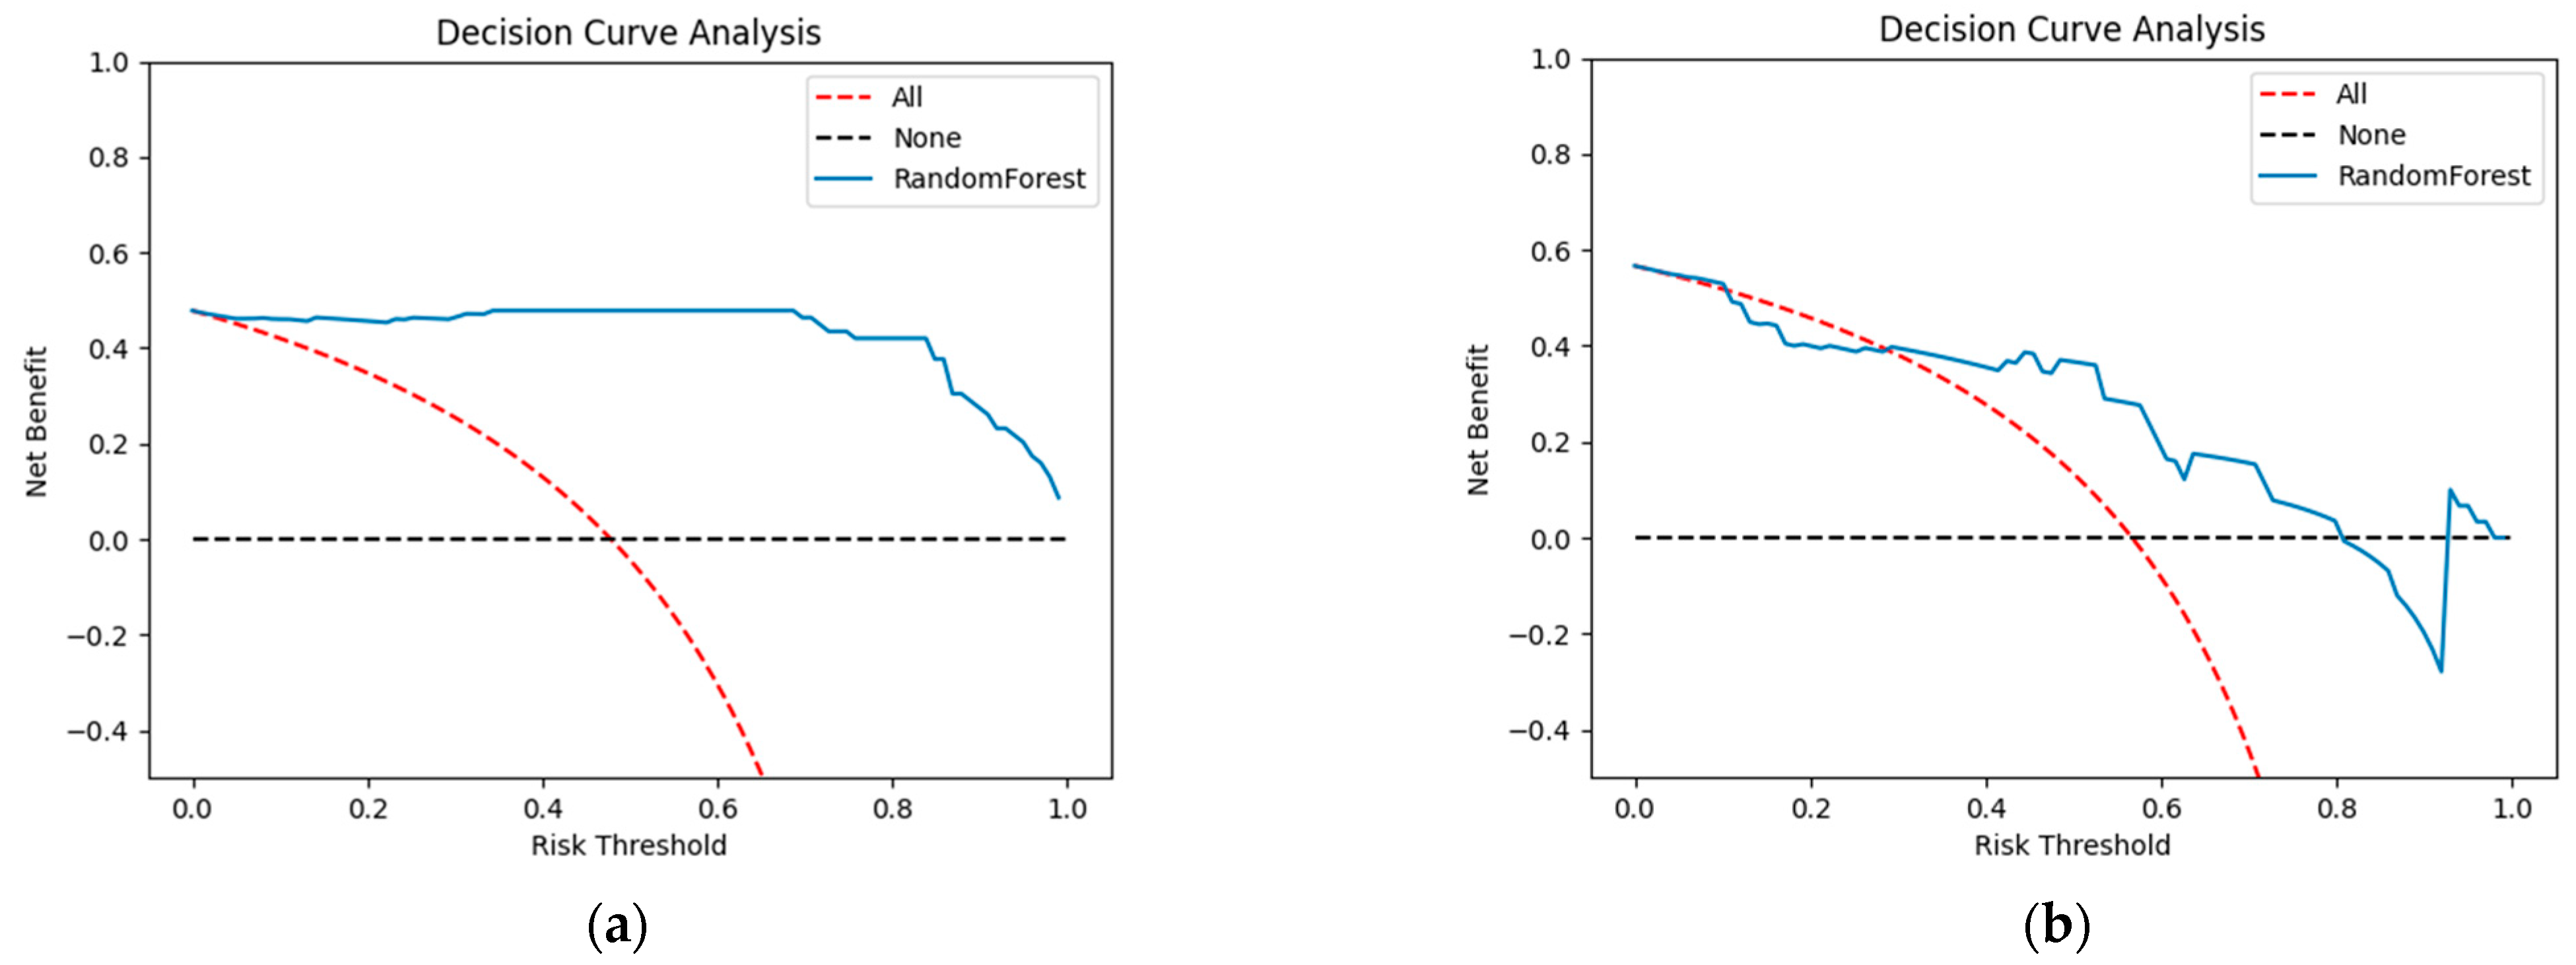

3.3. Model Evaluation